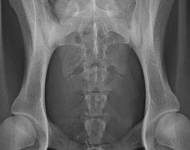

MVDr. Meloun: Lumbosakrální přechodový obratel